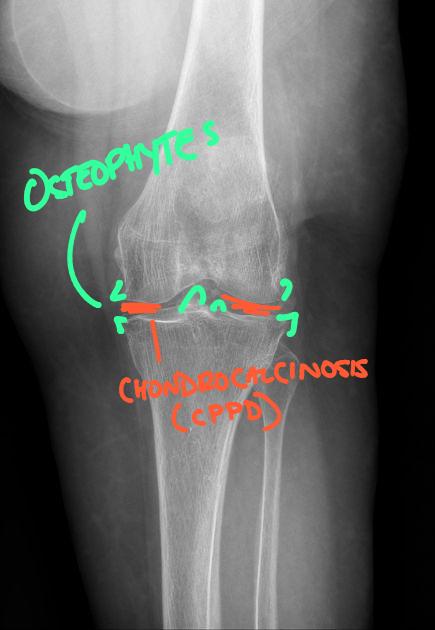

Chondrocalcinosis and CPPD: Kinetic Radiology

DACBR’s Guide to Chondrocalcinosis (CPPD) for Chiropractors

February 6, 2026

Read More »

Chondrocalcinosis and CPPD: A Diagnostic Imaging Guide for Chiropractors, Primary Care, and Urgent Care Overview Calcium pyrophosphate deposition disease (CPPD)

Read More